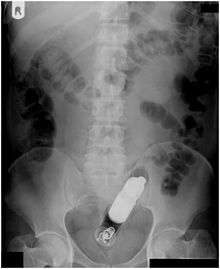

Rectal foreign bodies are large foreign items found in the rectum that can be assumed to have been inserted through the anus, rather than reaching the rectum via the mouth and gastrointestinal tract. Smaller, ingested foreign bodies, such as bones eaten with food, can sometimes be found stuck in the rectum upon x-ray.

Rectal foreign bodies, and amateur attempts to remove them, can result in perforation of the bowel, which is a life-threatening medical emergency. Rectal foreign objects are also the subject of a number of urban legends.